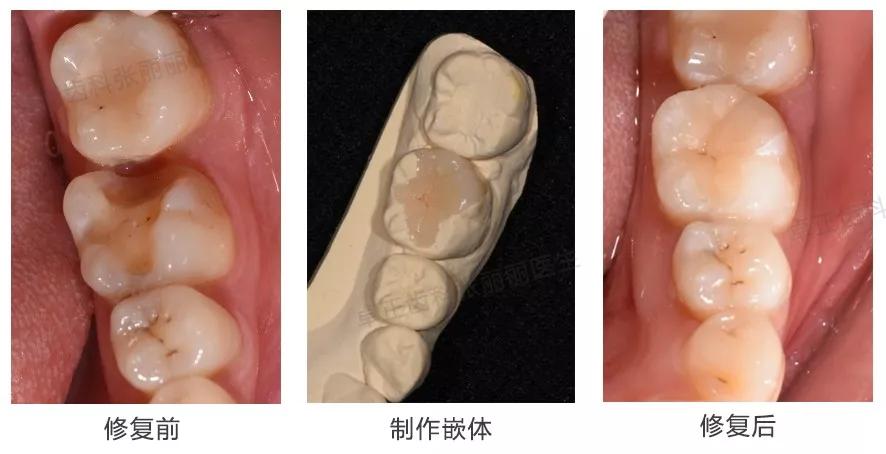

▍ 嵌体

当后牙牙体缺损较大、充填物反复脱落、较大邻面龋坏或缺损,同时患牙又是活髓时,建议嵌体修复。当缺损范围更大,需要覆盖部分或全部牙尖时,称为高嵌体。有关嵌体修复的优点及流程等可参考《牙齿缺了一大块,还能补上吗?》。

临床案例:患者多年前左下6充填治疗,继发龋,去净旧充填体及龋损后,见牙齿缺损较大,选择嵌体修复。